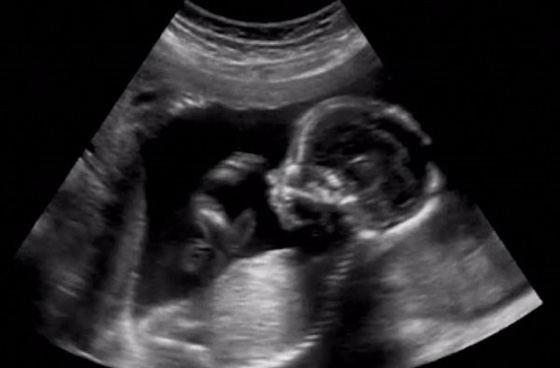

"ولد او بنت؟"، سؤال دائمًا ما تواجهه المرأة الحامل من معظم المحيطين بها، ونظرًا لأن الأطباء لا يستطيعون تحديد نوع الجنين بدقة إلا بعد 20 أسبوعًا من الحمل، فالمرأة لا تستطيع في الغالب الإجابة عن هذا السؤال رغم فضولها لمعرفة نوع الجنين قبل أى شخص آخر. اليكم مجموعة من الطرق التي تستطيع المرأة بفضلها معرفة نوع الجنين قبل زيارة الطبيب، هل هو بنت او ولد، ومن بينها:

يقوم طبيب النساء بإجراء اختبار للاستماع لنبض قلب الطفل، فإذا كانت ضربات القلب 140 نبضة في الدقيقة فيما فوق فهذا يشير إلى أن نوع الجنين طفلة، في حين أن معدل ضربات القلب الأقل من 140 نبضة في الدقيقة يشير إلى العكس.